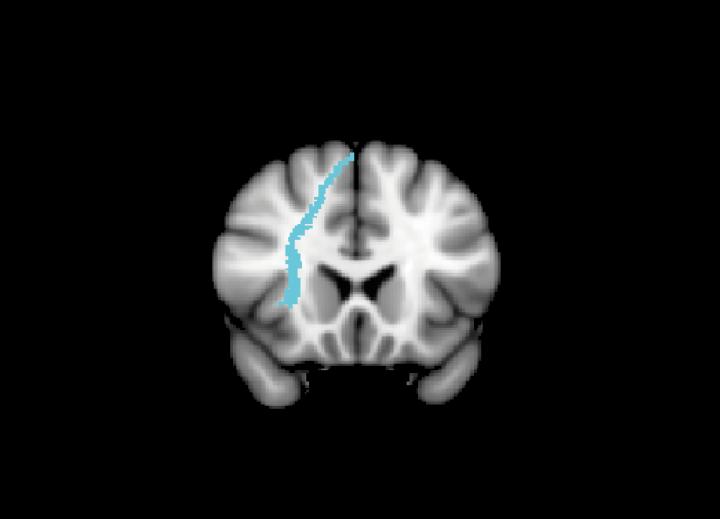

They found that differences in the makeup of the brain's white matter - the tissue deep in the brain and rich in the branching 'tails' of nerve cells - were key. The research revealed that those who had more connectivity in the regions being stimulated were more likely to respond better to the treatment.

However, when they analysed MRI scans, they found that those participants with highly-connected white matter in the brain region being stimulated responded best to the treatment, and those who had damaged or less-connected regions of white matter showed less improvement.

"We found that people with stronger white matter connections in their brain had better improvement with stimulation," Dr Li explained. "This might be an important reason why previous studies have found that some people benefit from stimulation, whilst others don't and means we can start using brain stimulation in a more personalised way."